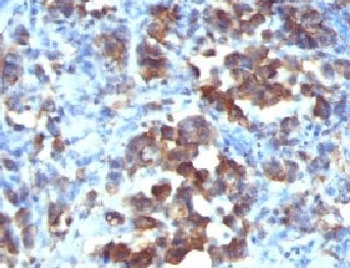

IHC: Formalin-fixed, paraffin-embedded human gastric carcinoma stained with Cdc20 antibody (CDC20/1102)

IHC: Formalin-fixed, paraffin-embedded human tonsil stained with Cdc20 antibody (CDC20/1102)